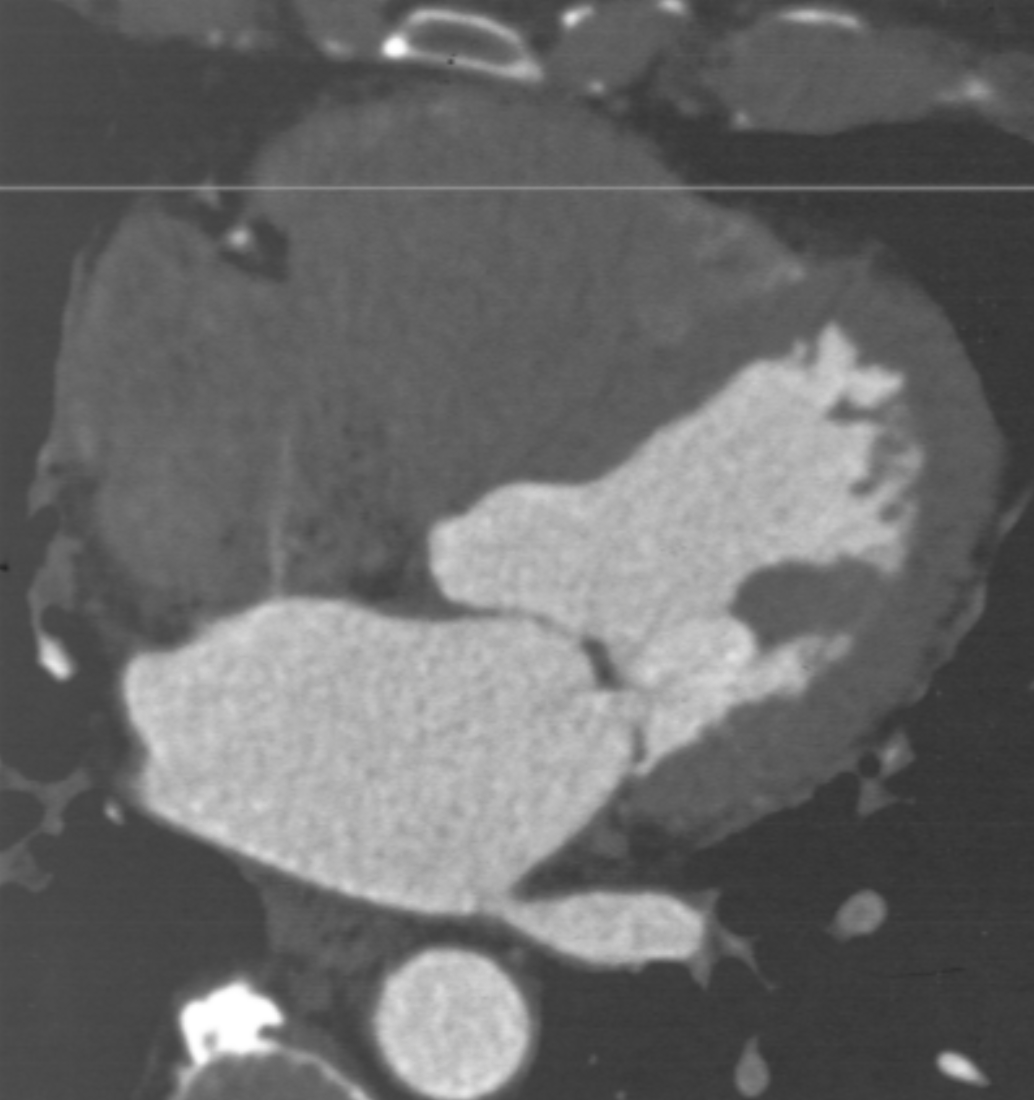

Describe the finding:

Microvascular obstruction